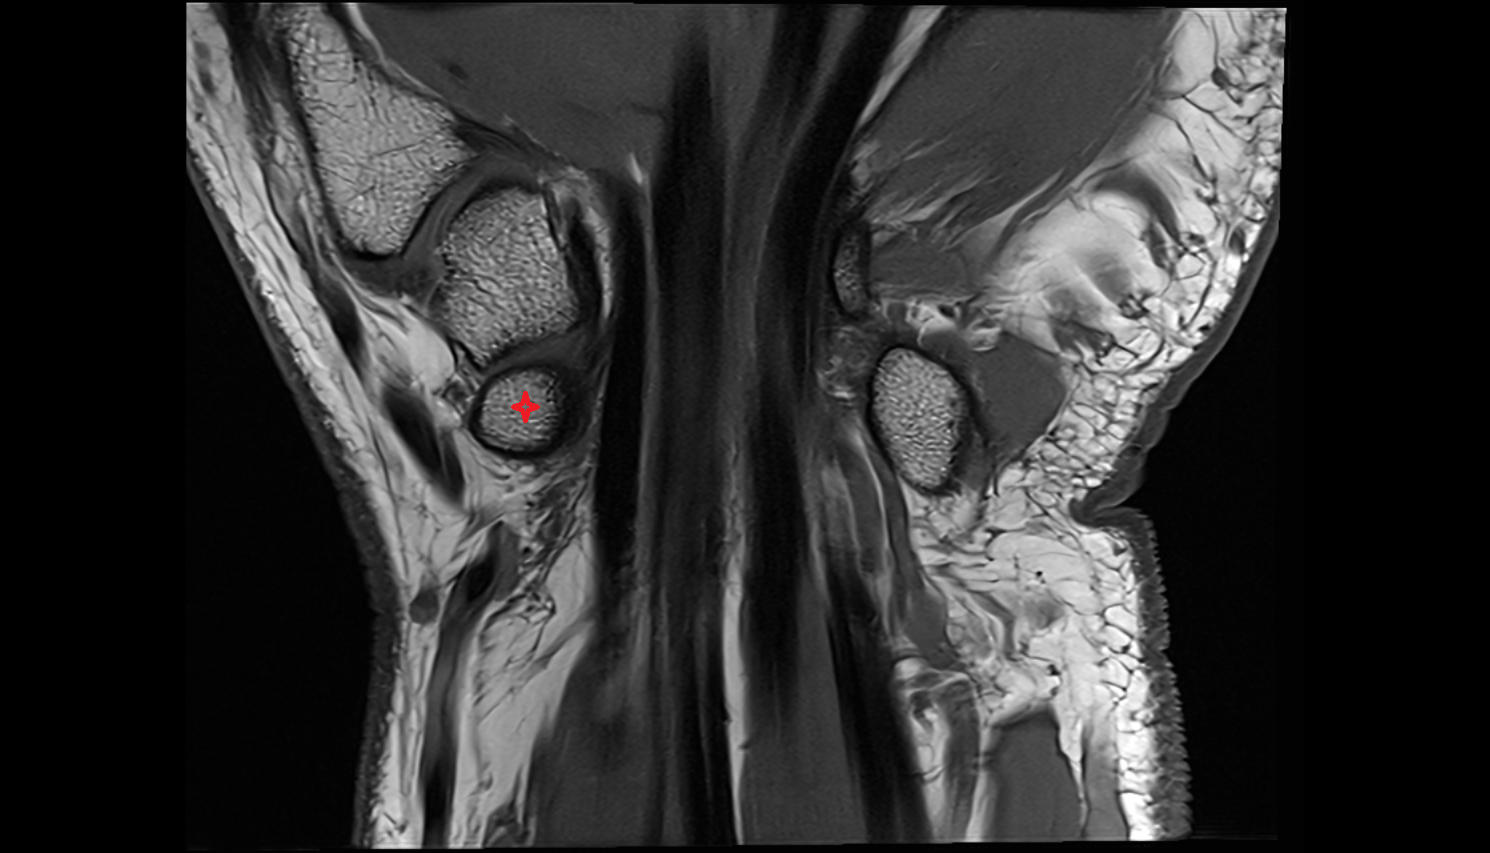

- Hip joint

- Head of femur

- Neck of femur

- Acetabulum

- Acetabular labrum